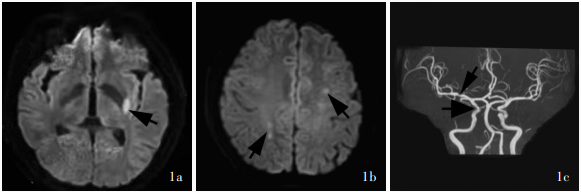

Dupont SA , Dispenzieri A , Mauermann ML , Rabinstein AA , Brown RD Jr . Cerebral infarction in POEMS syndrome: incidence, risk factors, and imaging characteristics. Neurology, 2009, 73: 1308- 1312.

doi: 10.1212/WNL.0b013e3181bd136b

Sugiyama A , Yokota H , Misawa S , Mukai H , Sekiguchi Y , Koide K , Suichi T , Matsushima J , Kishimoto T , Tanei ZI , Saito Y , Ito S , Kuwabara S . Cerebral large artery stenosis and occlusion in POEMS syndrome. BMC Neurol, 2021, 21: 239.

doi: 10.1186/s12883-021-02260-2

Takahashi Y , Mochizuki Y , Nakamura K , Katoh N , Sekijima Y . Moyamoya disease-like cerebrovascular stenotic lesions are an important phenotype of POEMS syndrome-associated vasculopathy. Intern Med, 2022, 61: 1603- 1608.

doi: 10.2169/internalmedicine.7701-21